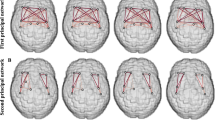

NBS identified two disrupted subnetworks (threshold = 3.0) among the MS, NMOSD, and HC groups (Table 4, Fig. 1A, Supplementary Fig. S2). The first subnetwork (subnetwork 1, p < 0.001) consisted of regions mostly located in the left temporo-parieto-occipital lobes, although the precuneus, cuneus, superior occipital gyrus, and calcarine cortex had bilateral involvement. Post-hoc tests indicated that compared with HC, the MS group had significant decreases in most edges of subnetwork 1 (28 out of 29 edges); however, in NMOSD only about half of the edges (13 out of 29 edges) were significantly decreased (Fig. 1B,C). Some edges were more disrupted in the MS group than in the NMOSD group, which were the connections between the left hippocampus and fusiform gyrus, between the fusiform gyrus and amygdala, between the superior temporal and inferior temporal gyri, and between the right precuneus and paracentral lobule (Fig. 1D). The second subnetwork (subnetwork 2, p = 0.028) was only disrupted in the MS group and was generally located in the inferomedial temporal region and consisted of five connections between the hippocampus, parahippocampal gyrus, fusiform gyrus, and thalamus in the right hemisphere. Compared with the NMOSD group, most edges (four out of five edges) were significantly disrupted in the MS group. We also identified that several edges of the disrupted subnetworks were associated with disease duration or EDSS score in the MS and NMOSD groups (Supplementary Table S4).

The two disrupted subnetworks in the multiple sclerosis (MS) and neuromyelitis optica spectrum disorder (NMOSD) groups as identified through network-based statistics. Significantly different connections between (A) three groups (MS, NMOSD, healthy controls [HC]), (B) MS and HC, (C) NMOSD and HC, and (D) MS and NMOSD were displayed; each edge was disrupted in MS or NMOSD compared with HC and there were no edges with increased edge weights in NMOSD compared with MS. The left column displays the lateral view of the left hemisphere, the middle column displays the transverse views of both hemispheres, and the right column displays the lateral view of the right hemisphere. The blue and red circles are the brain regions of subnetworks 1 and 2, respectively. The orange lines are the edges that connect each region. HIP hippocampus, PHG parahippocampal gyrus, AMYG amygdala, CAL calcarine fissure, CUN cuneus, LING lingual gyrus, SOG superior occipital gyrus, MOG middle occipital gyrus, FFG fusiform gyrus, SPG superior parietal gyrus, ANG angular gyrus, PCUN precuneus, PCL paracentral lobule, THA thalamus, STG superior temporal gyrus, TPOsup temporal pole: superior temporal gyrus, MTG middle temporal gyrus, TPOmid temporal pole: middle temporal gyrus, ITG inferior temporal gyrus.

Two subnetworks that characterized the structural connectivity abnormalities in the MS and NMOSD groups were also identified. Subnetwork 1 consisted of broad regions in the temporo-parieto-occipital lobes (mostly on the left side) and encompassed a part of default-mode, visual/visuospatial, and memory systems. Disrupted edges included decreased strength nodes, which were the left fusiform gyrus, left precuneus, left superior parietal gyrus, and the right superior occipital gyrus. Several disrupted edges, including the connection between the right and left precuneus, were significantly associated with EDSS score or disease duration in both disease groups. Subnetwork 2 consisted of five edges between the hippocampus, parahippocampal gyrus, fusiform gyrus, or thalamus in the right hemisphere, which were the right-side counterparts of those in subnetwork 1. The weights of most edges (four out of five) were negatively associated with the duration of MS. A previous study of WM structural networks in MS found decreased efficiency in brain regions related with default-mode, visual, memory, and language function11. Within these subnetworks, all connections except for one were disrupted in the MS group. However, in the NMOSD group there was relatively less disruption of the short connection between the thalamus and inferomedial temporal regions, including edges between the thalamus, hippocampus, parahippocampal gyrus, amygdala, fusiform gyrus, and inferior and superior temporal gyri. These regions overlapped with brain regions that had decreased local efficiencies in MS than in NMOSD.